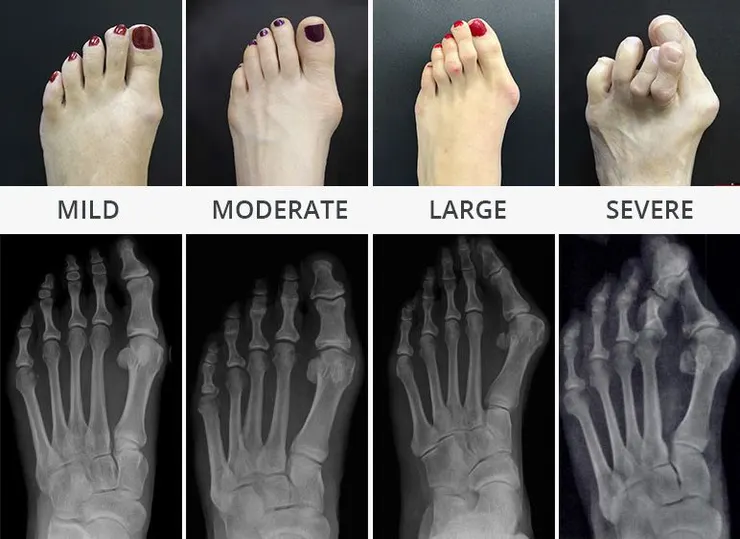

角度分級

第一蹠骨以及第二蹠骨最為夾角( IMA ),而正常小於 15~20 度還算合理範圍

- 輕度:拇指外翻角度 20~30度之間,IMA 9~11 度

- 中度:拇指外翻角度 30~40 度之間,IMA 11~18 度

- 重度:拇指外翻角度 > 40 度,IMA > 18 度